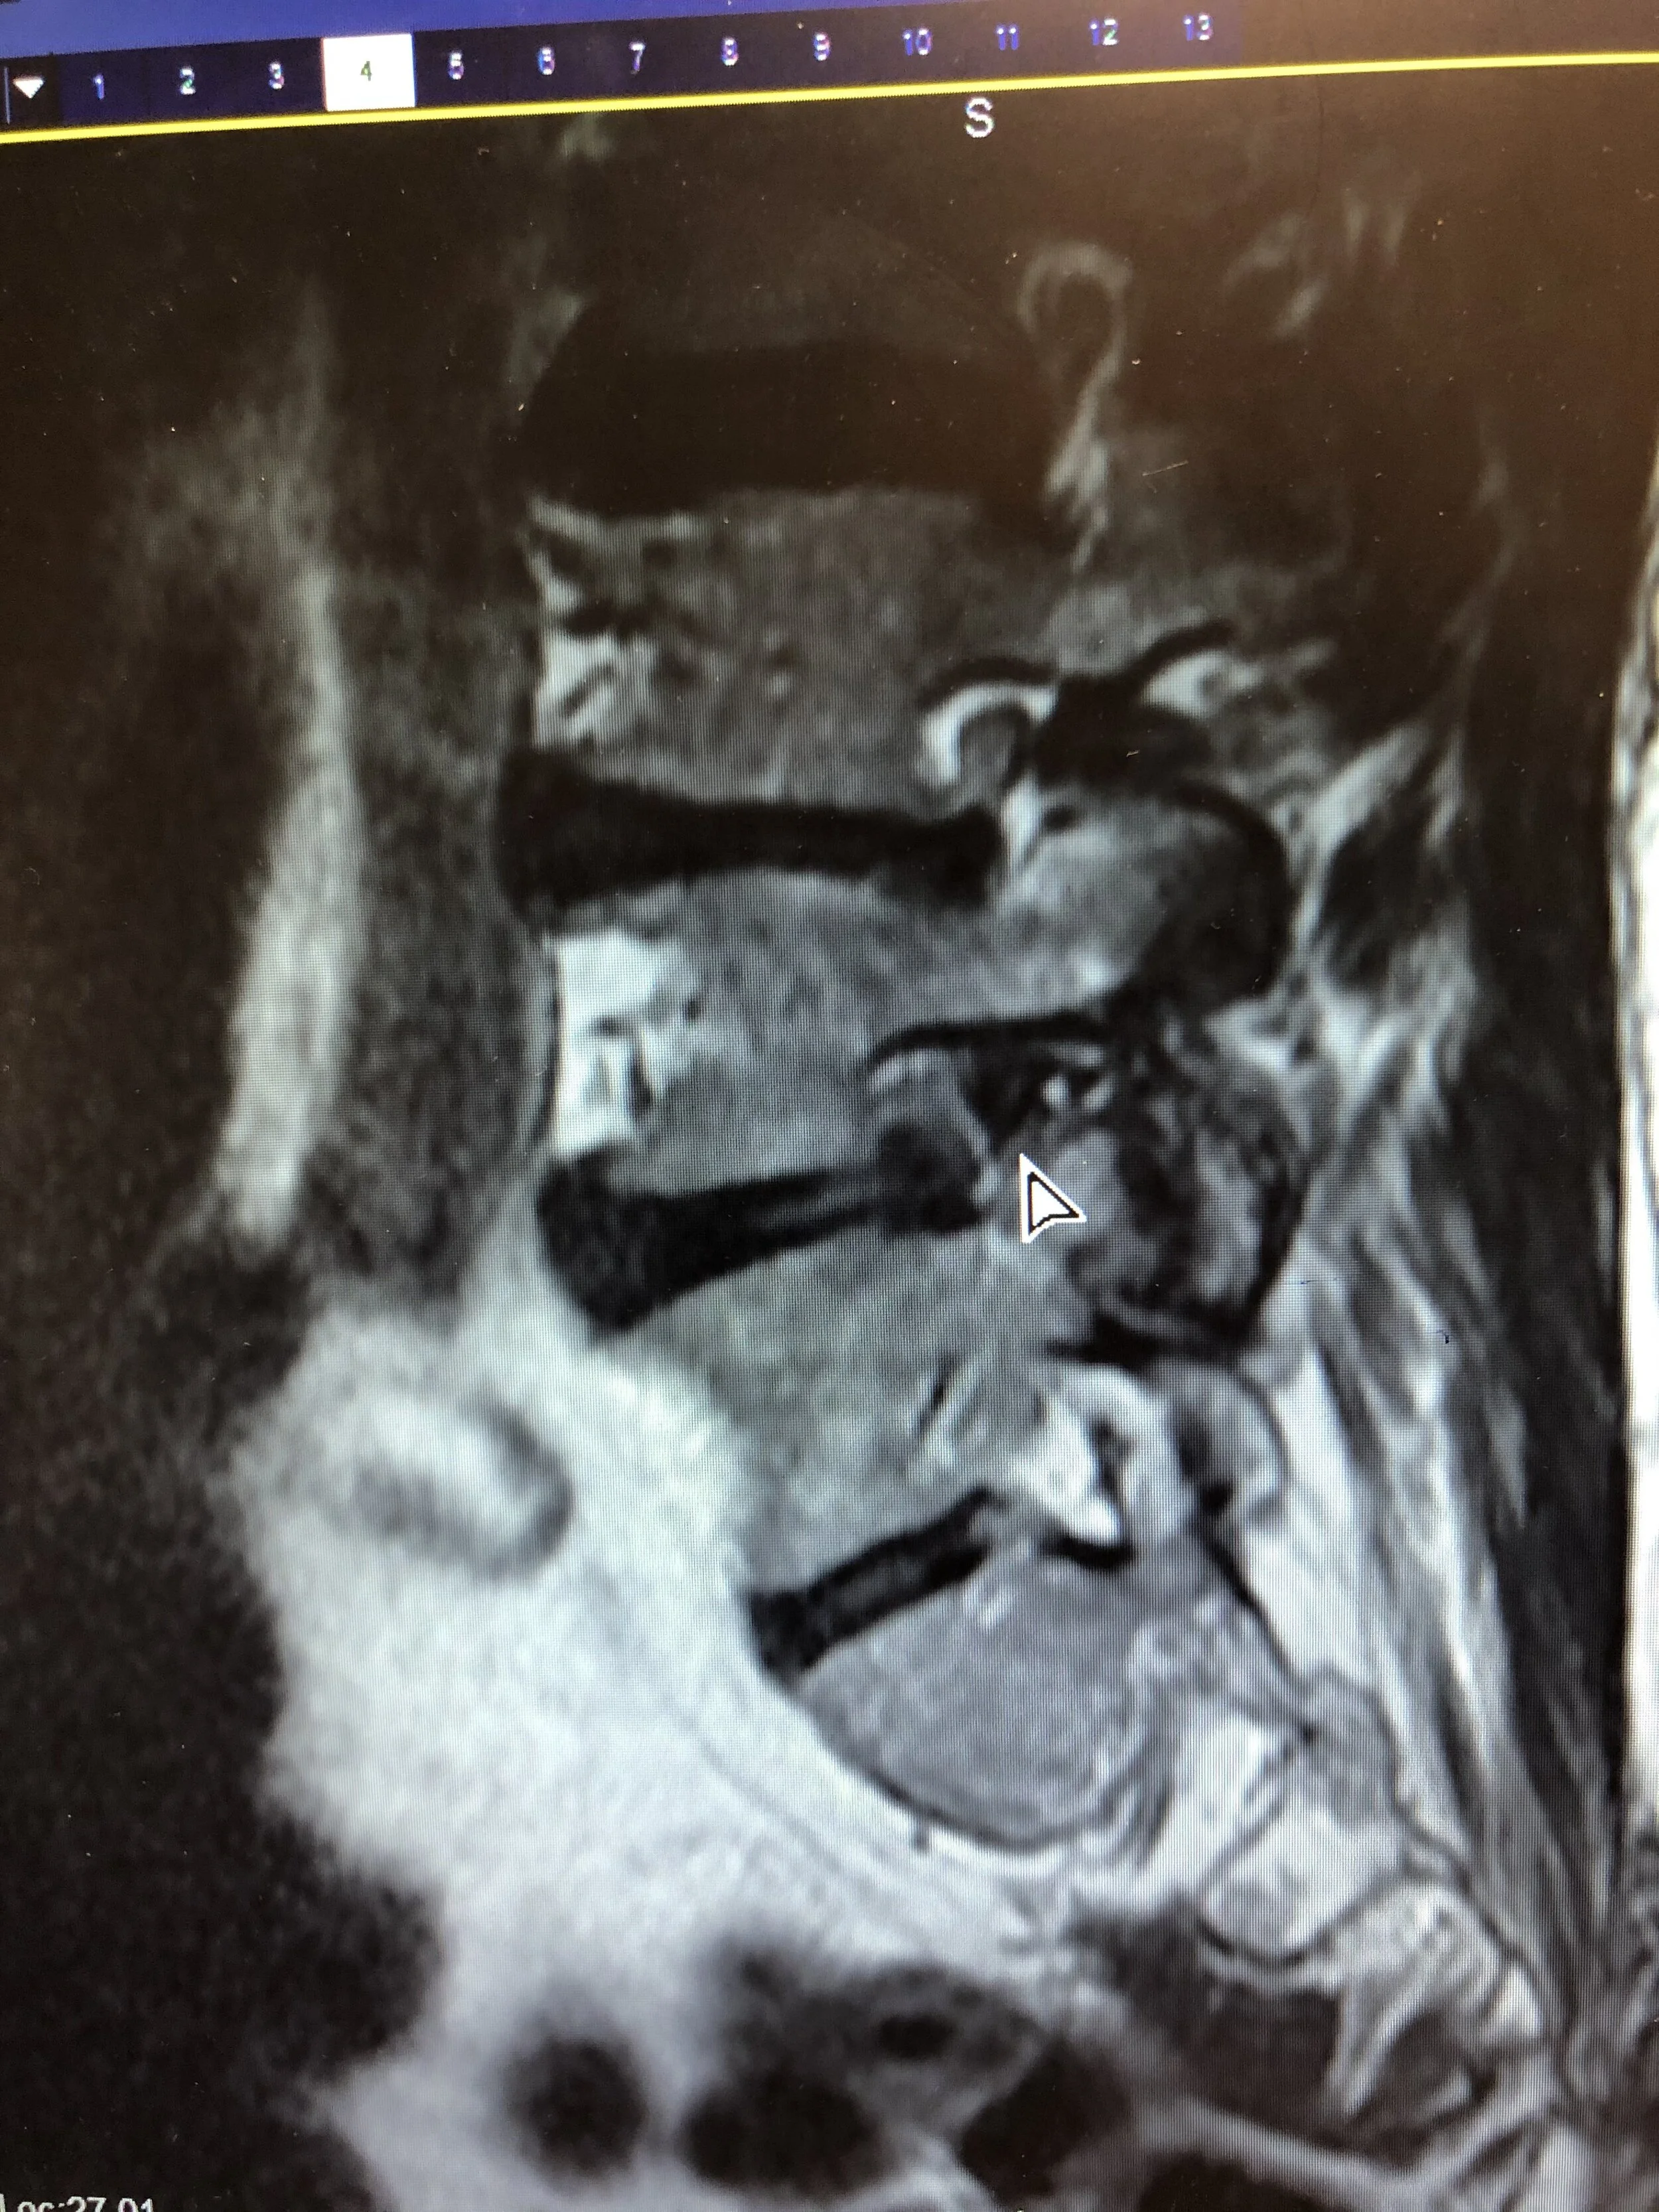

In these troubled times, our walks have been curtailed while my orthopedist tries to find the nerve that’s pinched in my spine & the treatment for it. An epidural has worked wonders. We’ll soon be back to these lovely walks but with grand kids in tow.